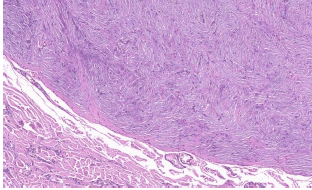

O Tumor muscular liso de potencial maligno incerto do corpo uterino é uma categoria heterogênea. Em relação a esta entidade patológica, assinale a alternativa correta.